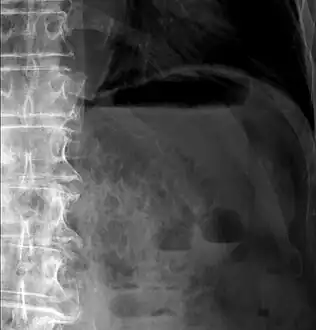

Close-up of intestine of infant showing necrosis and pneumatosis intestinalis (autopsy)

Differential diagnosisnecrotizing enterocolitis

Pneumatosis intestinalis (also called intestinal pneumatosis, pneumatosis cystoides intestinalis, pneumatosis coli, or intramural bowel gas) is pneumatosis of an intestine, that is, gas cysts in the bowel wall.[1][2] As a radiological sign it is highly suggestive for necrotizing enterocolitis. This is in contrast to gas in the intestinal lumen (which is relieved by flatulence). In newborns, pneumatosis intestinalis is considered diagnostic for necrotizing enterocolitis, and the gas is produced by bacteria in the bowel wall.[3] The pathogenesis of pneumatosis intestinalis is poorly understood and is likely multifactorial. PI itself is not a disease, but rather a clinical sign. In some cases, PI is an incidental finding, whereas in others, it portends a life-threatening intra-abdominal condition.